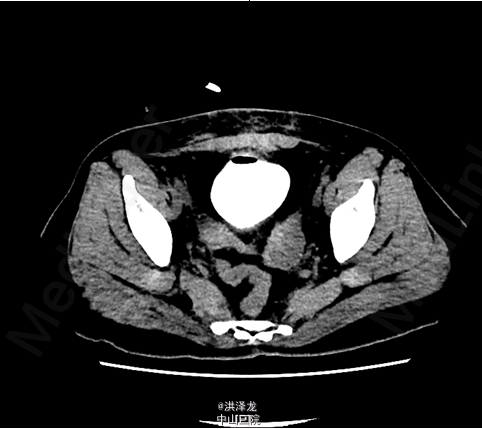

查体:外生殖器发育正常,尿道外口未见异常,可见少量水样分泌物持续从阴道口流出,未见盆腔脏器脱出。 膀胱造影后盆腔CT平扫示:子宫切除术后改变,膀胱阴道瘘。诊断膀胱阴道瘘基本明确,原因考虑子宫全切术损伤。

入院后完善相关检查,术前检查未见手术禁忌,行腹腔镜下经膀胱膀胱阴道瘘修补术,术中见膀胱阴道瘘道内一线结,予以拆除,术程顺利,术后安返病房。术后予抗感染、营养补液等治疗。复查膀胱造影后盆腔CT平扫示:未见明确外漏。